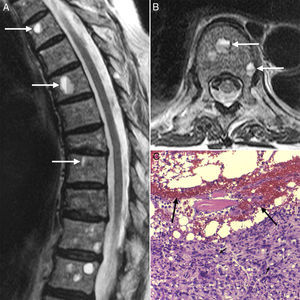

A 76-year-old female patient came to the clinic due to lumbar spine pain and weight loss, which had progressed over the past 6 months. She had been diagnosed with systemic sclerosis (SS) and interstitial lung disease 5 years prior and had been treated with cyclophosphamide induction therapy for 18 months (6 monthly cycles and 4 trimestral ones), followed by azathioprine and low dose steroid as maintenance treatment. Upon examination, the patient presented cachexia and diffuse pain on spinous process palpation. Spinal X-rays showed anterior vertebral body collapse at D8 and a magnetic resonance (MR) revealed multiple round lesions with a fluid-fluid level, with a hyperintense signal on the superior level potentiated sequence on T2 and an intermediate signal on T1, with hypointense signal on the inferior level of both sequences (Fig. 1A and B). A bone biopsy revealed that the lesions were metastasis from a poorly differentiated signet ring cell adenocarcinoma, surrounding hemorrhagic content (Fig. 1C). From an immunohistochemical point of view, the tumor cells expressed cytokeratin 7 and protein 15 of cystic disease liquid, indicating a likely breast cancer origin. However, no primary tumor was found in follow-up, which included a bilateral mastorgraphy, a craneo-cervical and thoraco-abdomino-pelvic computed tomography, a complete radionucleide bone scan, an endoscopy and a colonoscopy. The patient was treated with paclitaxel plus carboplatin, third level analgesia, zolendronate and palliative radiotherapy, remaining stable for 6 months afterward.

Dorsolumbar spine magnetic resonance showing, in sagital (A) and axial (B) projections of a T2 potentiated sequence, the presence of multiple vertebral lesions with typical fluid–fluid levels, hyperintense superiorly and hypointense inferiorly. A bone biopsy (C) revealed that these lesions corresponded to metastasis of a poorly differentiated adenocarcinoma with signet ring cells (arrowheads), surrounding a hemorrhagic content (arrows) (hematoxilin-eosin 10×).